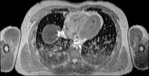

Visible Human male: Sectio transversalis 1460

CT

NMR

Pd                          / T2 \                         T1